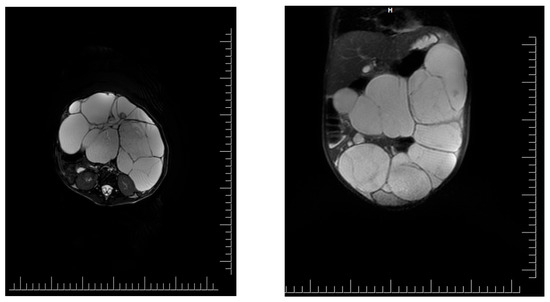

- Superior, the lesion has a mass effect on the liver, spleen, stomach, and transverse colon, which appeared to be displaced superiorly, with the border of separation;

- Inferior, the lesion comes in contact with the upper wall of the urinary bladder, with the limit of separation;

- Posteriorly, the lesion comes into contact with the intestinal loops

- Anteriorly, it comes in contact with the anterior abdominal wall